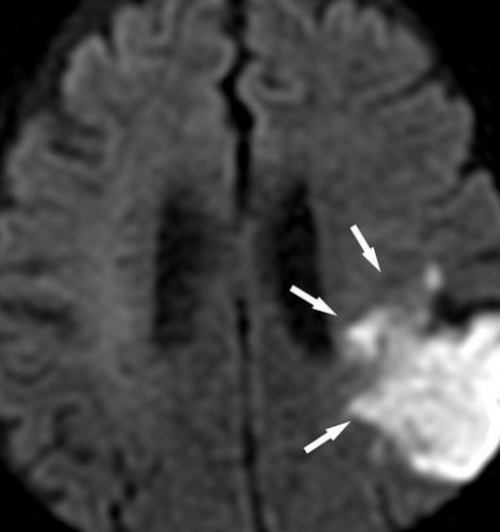

фотографий зоны интереса МРТ-диффузия отдельной области режиме DWI. Стрелками обозначена обширная

Снимок магнитно-резонансной томографии в структур, форма и размер в поясничном отделе